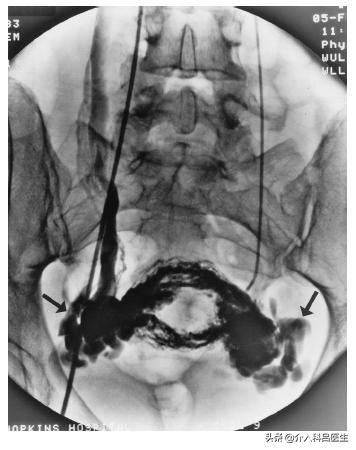

如果体检时发现下腹部(耻骨联合处上方)有压痛,下腹部两侧存在深压痛,建议患者完善盆腔的影像学检查。卵巢静脉曲张各种影像检查都有典型表现,首选简单无创的彩超检查,以及核磁共振成像。核磁共振成像检查不仅可以全面诊断,也可为后续介入栓塞治疗提供精确指导,并用于术后随访。

该病对女性健康和家属幸福影响较大,内科对该病缺乏有效的药物治疗,外科手术采用切除子宫的方法,但不会减轻疼痛症状,却加重了患者的心理负担。在20世纪80年代,人们开始尝试对卵巢曲张静脉结扎的方法,具有一定疗效,但创伤大,患者不易接受。进入21世纪后,随着介入治疗技术的发展,应用弹簧圈栓塞卵巢静脉、聚桂醇硬化盆腔静脉的方法,具有创伤小、技术安全的特点,且疗效可靠。卵巢静脉栓塞技术成功率高达96%以上,栓塞后有效率达75%以上。栓塞应始于卵巢静脉的盆腔起始部,直至卵巢静脉——肾静脉开口下方水平,双侧卵巢静脉和与疾病相关联的异常血管都要进行栓塞。卵巢静脉栓塞越彻底,疗效越好,越不容易复发。卵巢静脉介入栓塞治疗在月经干净后一两天进行,经股静脉穿刺,导管经左肾静脉进入左侧卵巢静脉,插管至卵巢静脉最远端,对静脉进行彻底栓塞。栓塞后2小时~4小时,患者便可以下床活动,两三天后患者即可康复出院。待患者症状减轻、消失后,便可以进行正常*生活性**。